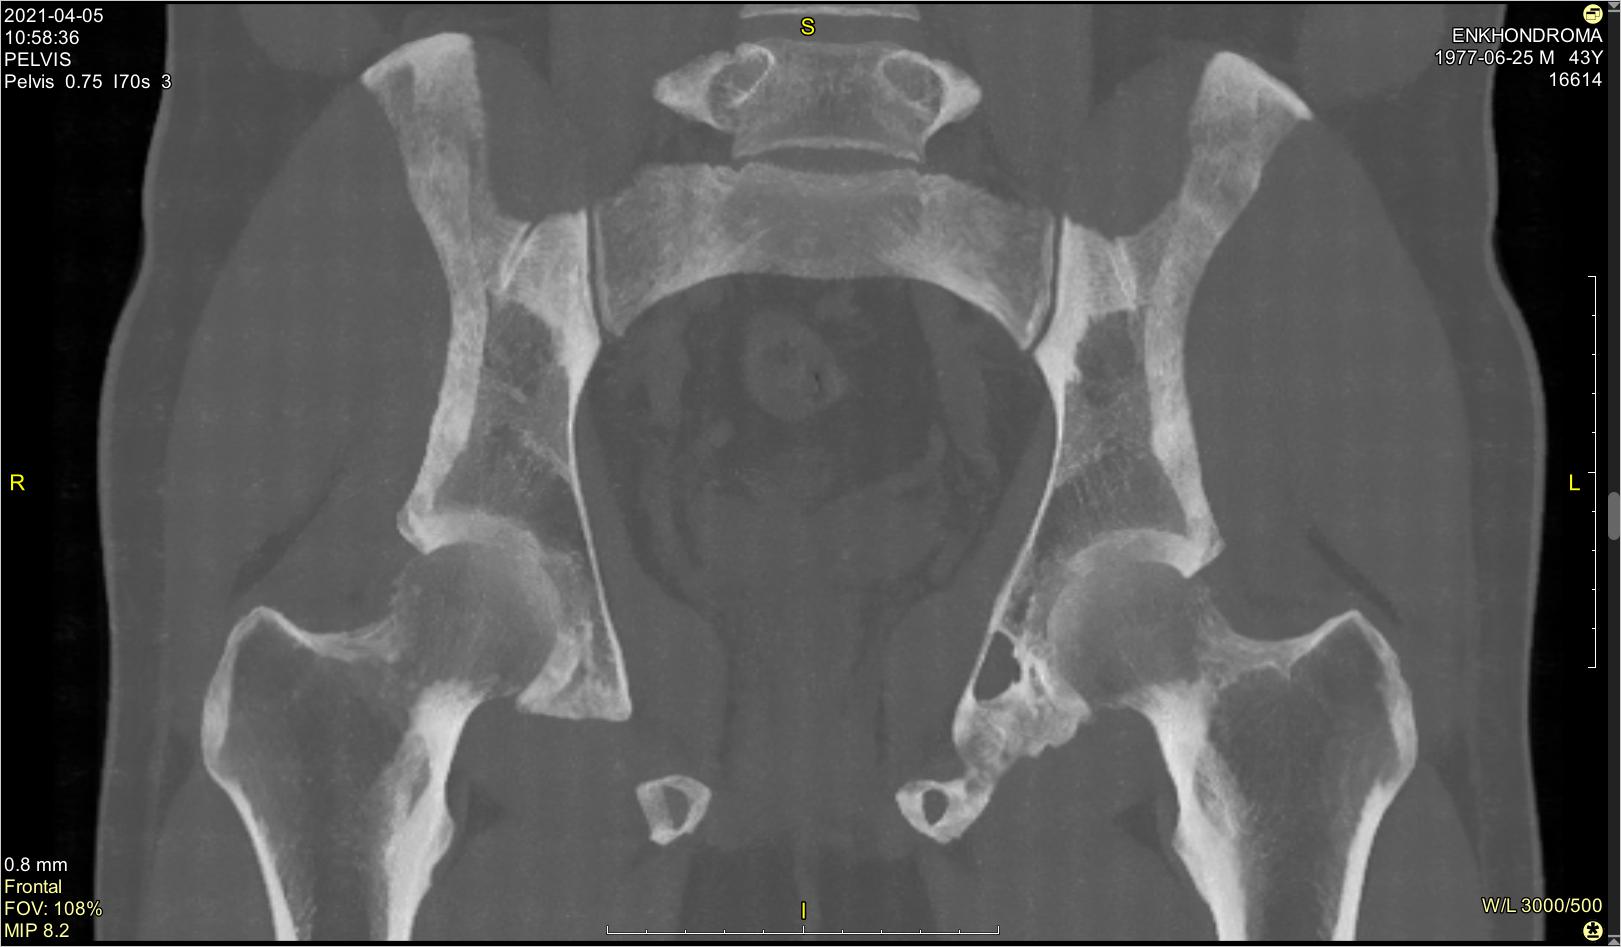

Девочка, 4-5лет, направлена с "о. бронхитом?"( как обычно). "Хрипов нет", жалобы на Т до 37,5. Лечится 5дней.

Рентгенолог пишет - норма. А Ваше мнение?

Так тут же пневмония в расцвете сил! Я даже в позитиве выложил. Народ кричал - так лучше видно!

А вот через 10 дней "по пневмониестее" выглядит. Справа, в нижнемедиальном поле. А корни широкие - важный признак пневмонии у детей. А ещё ( меня так учили)во имя симметричной укладки теперь не считается преступлением выполнить снимок ОГП лёжа, если нет иного выхода. Хотя стоя - предпочтительнее. Конечно, попадяются клиенты, которых " ни мытьём, ни катанием"...

Детей такого возраста снимаю стоя(без лаборанта работаю),дожидаюсь "мнгновения покоя" и жму на высокое.Вроде получается.Здесь-пневмония справа.Нужен дальнейший контроль.

Во втором-третьем межреберье справа в плащевой зоне в динамике "рассосалось".

В негативе снимок бледноватый получился, поэтому в позитиве лучше видно.